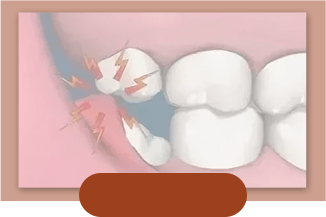

- NO.3 清洁不到位造成龋坏,智齿冠周炎、牙髓炎紧随而来。

- NO.4 位置不正把邻牙“顶坏” 导致第二磨牙的丧失。